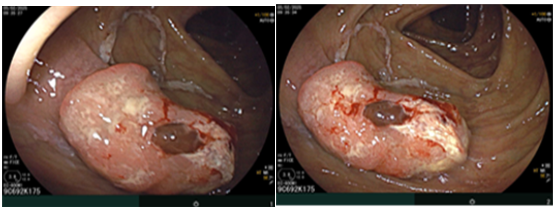

Sau đó bệnh nhân được nội soi dạ dày - đại tràng phát hiện đại tràng lên có khối lồi kích thước ~2.5cm, bề mặt nham nhở, cứng dễ chảy máu. Sinh thiết 03 mảnh. Giải phẫu bệnh: Ung thư biểu mô tuyến.

Hình 3. Tổn thương khối lồi xuất hiện ở vùng đại tràng lên

Nội soi đại tràng (thời điểm trước phẫu thuật T2/2025): Đại tràng lên có khối lồi kích thước ~2.5cm, bề mặt nham nhở, cứng dễ chảy máu.

Hình ảnh nội soi đại tràng thời điểm trước phẫu thuật.